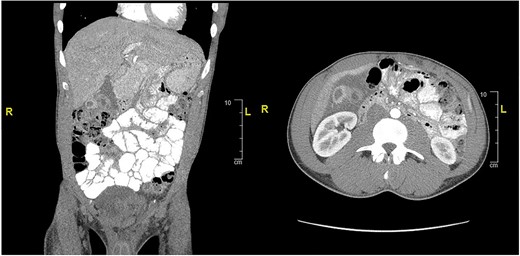

CT of abdomen and pelvis showing peripherally hyperdense septated collection within the porta hepatis with surrounding fluid signal attenuation likely representing an abscess seen around the gallbladder.

Case presentation #2: A 39-year-old male initially presented with acute cholecystitis (AC) with a markedly thickened wall with abscess formation, not amenable for drainage, treated with antibiotics with improvement, but later experienced recurrent biliary colic symptoms. Repeat computed tomography (CT) imaging (Fig. 4) 2 months later showed a peripherally hyperdense septated collection within the porta hepatis with surrounding fluid signal attenuation; likely representing an abscess seen around the gallbladder possibly secondary to gallbladder perforation due to neoplastic versus inflammatory pathology. Ultrasound showed chronic cholecystitis with cholelithiasis. The patient later underwent elective laparoscopic cholecystectomy. Intraoperatively, extensive adhesions from the liver to the gallbladder and the colon to the gallbladder were noted. The fundus of the gallbladder was densely adherent to the hepatic flexure with no dissection plane. The hepatic flexure felt firm, raising concern of a possible tumor or fistula. The decision was made to remove the right colon en-bloc with the gallbladder. The gallbladder was dissected free in the usual manner and a critical view was obtained. Once the gallbladder was freed, we proceeded with a laparoscopic right hemicolectomy with ileocolonic anastomosis. The specimen was evaluated on the back table; no tumor was seen, but there was what appeared to be an abscess cavity adherent between the gallbladder and colon filled with green stool-colored liquid. The patient tolerated the procedure well and was progressively advanced to regular diet postoperatively and discharged on postoperative Day 3. His final pathology of the operative specimen (Fig. 5) came back as acute on chronic cholecystitis with a micro-fistula between the gallbladder and the adjacent colon.